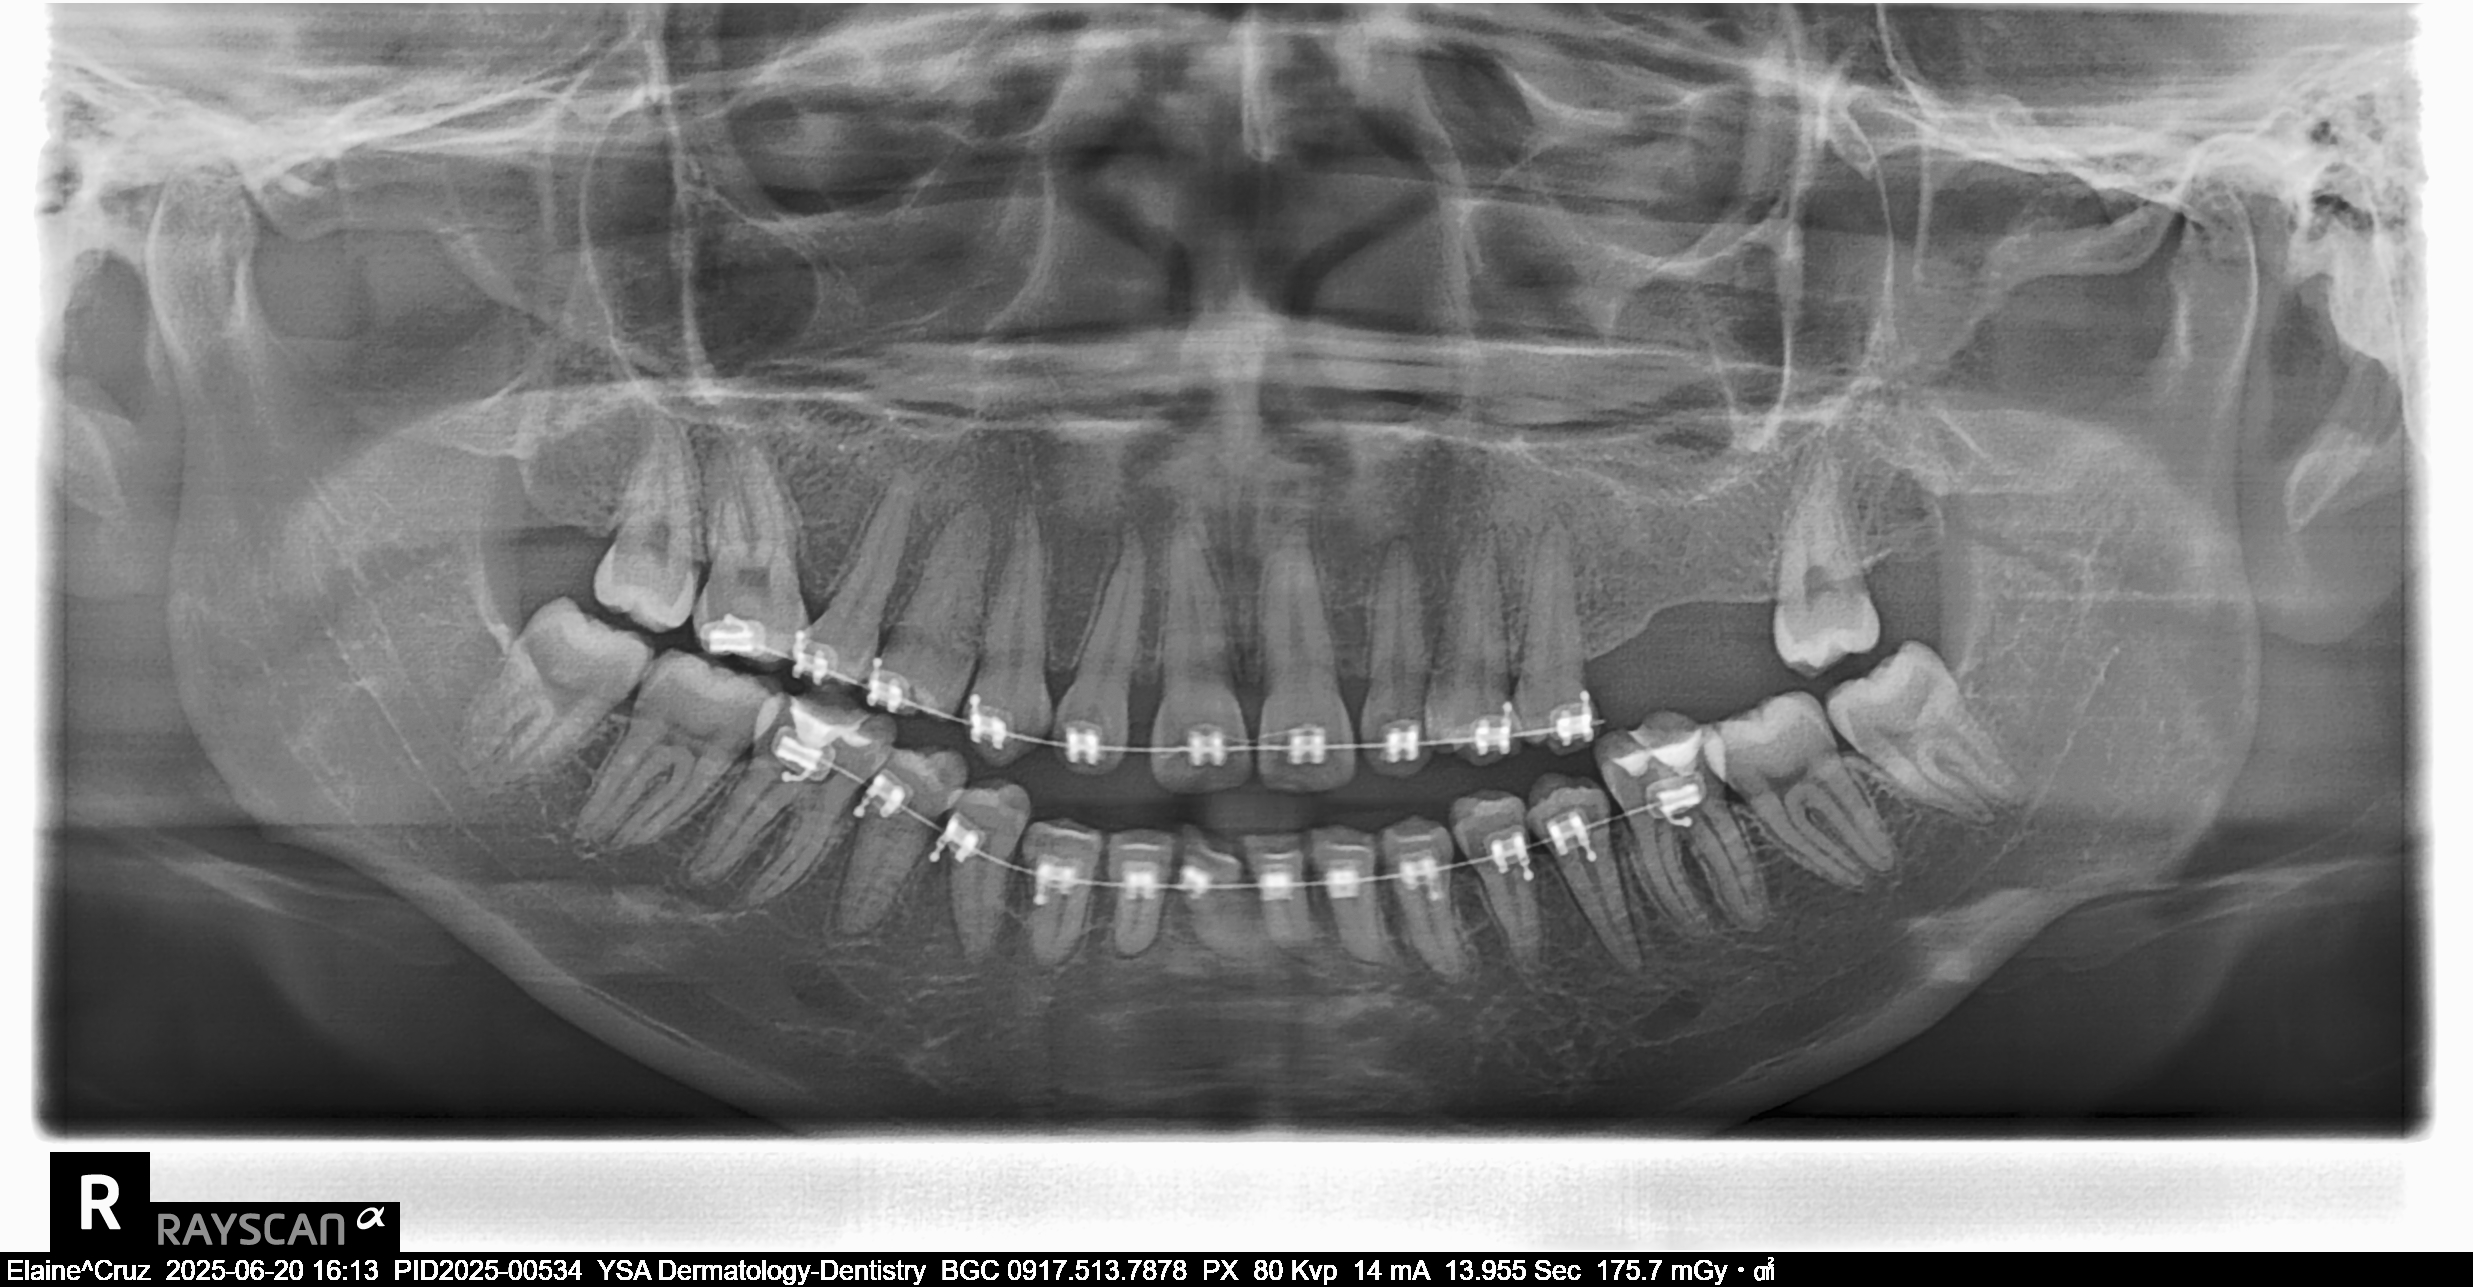

- Last Name

- Cruz

- First Name

- Elaine

- Middle Name

- Guevarra

- Birthdate

- December 20, 1998

- Age

- 26

- 02/06/25 MBT 0.22 slot 14 NITI U/L no BT on #26 free cleaning & free #34 O 03/11/25 Adj reattached #11,13,15,34 04/10/25 adj reattach #15 RW #41, #12 05/10/25 Adj same wire IPR #41-42,32 06/10/25 adj same wire L 16 NITI U reattached #45 07/15/25 Adj same wire 16 SS U 16 NITI L Reattached #11 08/22/25 Odontectomy #48 09/04/25 Suture removal 09/24/25 coil spring (open) on tooth #12-11 and 21-22 ligature wire #11-21 same wire Reattached #44 10/30/25 adjustment same wire chain #12 to #22 11/28/2025 Odontectomy #38 Suture 12/02/2025 Suture Removal Irrigate w/ Saline BlueM Gel PA xray 12/26/25 Adjustment 16 SS U/L class III fox 3.5oz chain all lower 01/21/26 Adjustment 18 SS upper w/ loop 16 SS lower 3/5/26 adj same wire

- file_0001_7.jpg